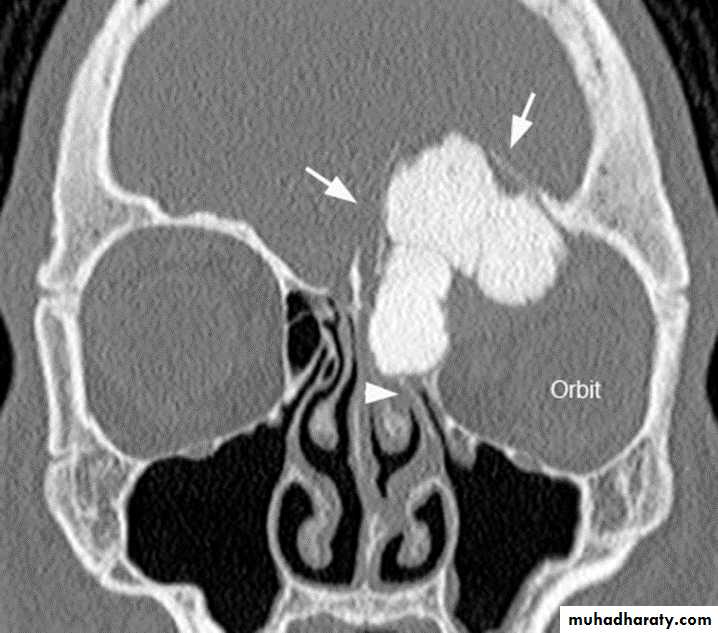

CT scan :

bone window setting is required(Window width \window level 3000\450 ) for optimum results (for specific bone details) .

1- Abnormality in complex bones as the spine, pelvis, face and skull.

Ankylosing spondylitis-early

(A) Serrated marginsof sacroiliac joints and peri articular sclerosis.

(B) CT scanning demonstrates bilateral sacroiliitis